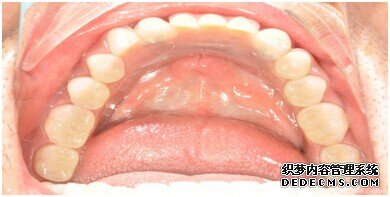

成功植入种植体后的效果图

种植体成功植入后的CT效果图

整个种植牙完成后的效果图

种植牙整个过程完成后,刘女士非常满意自己的牙齿,并且表示以后一定会遵照医生的嘱咐好好注意自己的口腔健康,每晚一定会好好刷牙,饭后漱口,当然也会注意保护这颗种植牙!